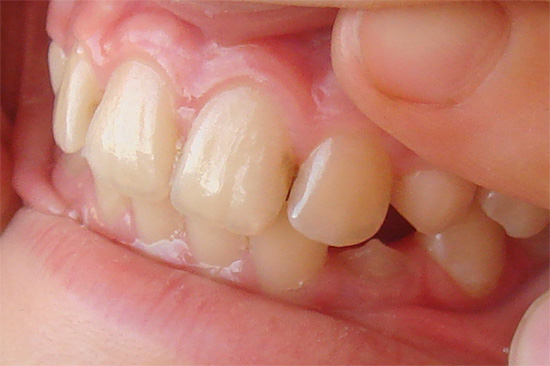

Nella maggior parte dei casi, al primo esame dei denti, le loro pareti (superfici) colpite dalla carie colpiscono. Spesso non si tratta di cavità, ma semplicemente di smalto grigio e appannato, che ha perso il suo aspetto sano a causa della demineralizzazione.

Spesso il dentista vede un "tunnel" tra i denti, ma la sonda potrebbe non passare nella cavità cariata interna nascosta a causa della densità dello spazio interdentale. Di solito, il medico mostra al paziente sfumature di smalto grigiastro nello specchio sullo sfondo della carie interna sviluppata e inizia il trattamento dei denti dopo l'anestesia.